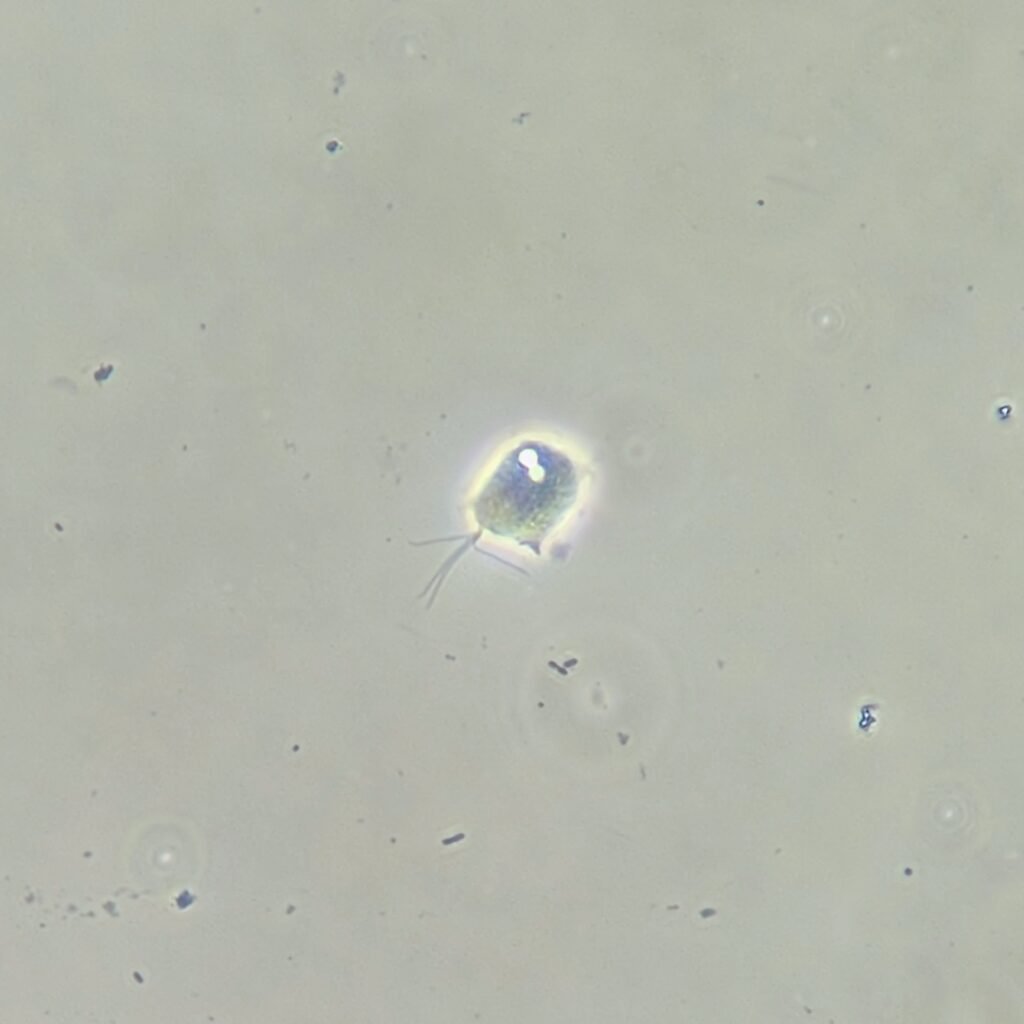

Trichomonas are pear-shaped and have four flagella. Motility is usually necessary for identification.

Trichomonas can look like a white blood cell when non-motile which is why motility is usually necessary to positively identify by microscopy.

Gallery